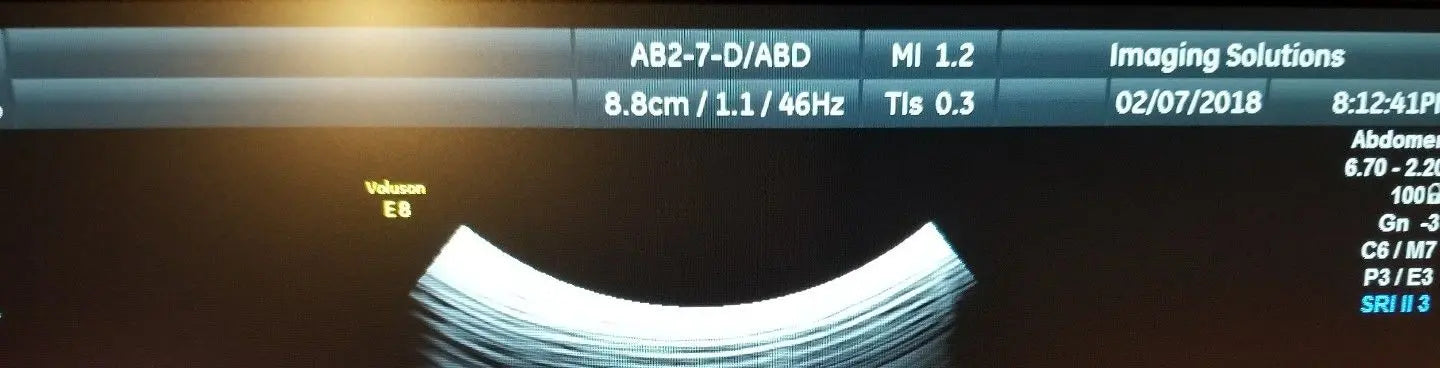

Exceptional Imaging Quality

The GE ultrasound probe, model AB2-7-D, is renowned for its superior imaging capabilities. It features advanced transducer technology that provides high-definition images, which are crucial for accurate diagnoses. This probe excels in various medical applications, including obstetrics and gynecology, allowing medical professionals to visualize internal structures clearly. Because of its cutting-edge design, clinicians can rely on the GE ultrasound probe for precise assessments, enhancing patient outcomes significantly.